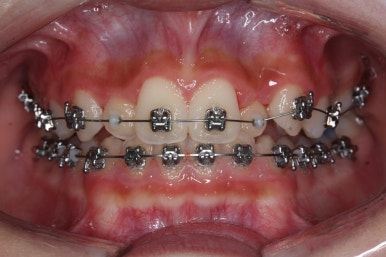

키다리아저씨치과에서 부산비발치교정 전후 사진 비교입니다.

치료 종료 시점에는 위아래 앞니 모두 안쪽에 유지장치를 붙이고 있는 것을 볼 수 있습니다.

교정 중에 양치가 잘 되지 않아 치료 후 모습에서 잇몸이 부어있는 모습도 보이는데 양치질을 잘 해주면 금방 좋아질 수 있습니다.

앞니가 매우 가지런해졌고 예뻐졌네요.

악궁확장장치 기간까지 포함하여 총 1년 4개월이 걸렸습니다.

삐뚤했었던 특히 안으로 쏙 들어가 있었던 작은 앞니가 개선되면서 웃는 모습이 많이 좋아졌습니다. 상대적으로 덧니처럼 보이던 송곳니의 느낌도 좋아졌네요.